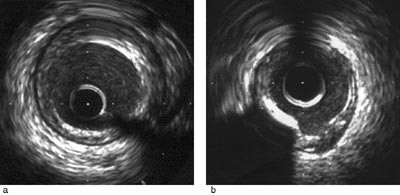

Når det avleires aterosklerotisk materiale i koronararterien vil dette bli synlig som en fortykkelse av intima. Ved ultralyd klassifiseres lesjonene som myke, fibrøse eller kalsifiserte etter graden av ekkotetthet i lesjonen (fig 2) (6). Det fleste arterielesjoner er fibrøse. Ved ultralyd blir et fibrøst plakk fremstilt som et område med heterogene, lyse ekko i intima med en ekkotetthet som likner på den man ser i adventitia (fig 2a). Myke lesjoner med svak ekkotetthet har man i plakk som har diffus lipidinfiltrasjon i intima og i fibromuskulære cellerike lesjoner.Det er de sterkt lipidholdige lesjoner som vanligvis gir akutt koronarsyndrom, og som derved kalles vulnerable plakk. Ved dagens ultralydteknikk kan lipidholdige lesjoner ikke tilfredsstillende skilles fra cellerike fibromuskulære lesjoner. Kalk i intima gir et intenst ekko med reflekterende skygge (akustisk skygge) (fig 2b). Påvisning av kalk er viktig fordi disseksjoner lett oppstår i overgangen mellom kalk og mykt plakk. Histologisk er de aterosklerotiske plakkene sjelden homogene, men består av en blanding av de ulike plakkomponeter. Tromber i arterier er synlig ved ultralyd som en grå, ikke homogen masse med uklar avgrensning mot lumen og lettest påvisbar på levende bilder der man tydeligere ser avgrensningen mot blodet.

Lumen i arterien er definert av grensen mellom blod og intima. Lumens diameter (mm) og areal (mm²) i tverrsnittsbildet beregnes etter kalibrering av måleenheten (fig 3). Stenoser blir målt i det området av arterien som er trangest (minimal lumendiameter og minimalt lumenareal). Ved måling av stenosegrad ved ultralyd blir minimalt lumen kalkulert i forhold til dimensjoner i et normalt segment (referansesegment) like proksimalt eller distalt for stenosen.

Karrets størrelse (diameter og areal) er definert som dimensjoner innenfor media (fig 3). Membrana elastica externa i grensen mellom media og adventitia gir større ekkorefleksjon enn media, og er derfor lettere å påvise enn media. I praksis brukes derfor membrana elastica externa som ytre begrensning for karet ved måling av karstørrelse, og arealet benevnes da totalt arterieareal. Siden media er en tynn struktur, vil arealet i det aterosklerotiske plakk være definert av totalt arterieareal minus lumens areal. Plakkets andel av arteriens areal ( %) er uttrykk for mengden aterosklerose i arterien og blir i engelsk litteratur omtalt som «plaque burden». Arterien kan gjennomgå remodellering med bevaring av lumen og utviding av arterieveggen (positiv remodellering) eller forsnevring av arterieveggen (negativ remodellering) i områder med aterosklerose (7). Derfor vil stenosegraden definert slik ikke være sammenfallende med stenosegrad målt angiografisk eller ved intrakoronar ultralyd med bruk av referansesegmenter.